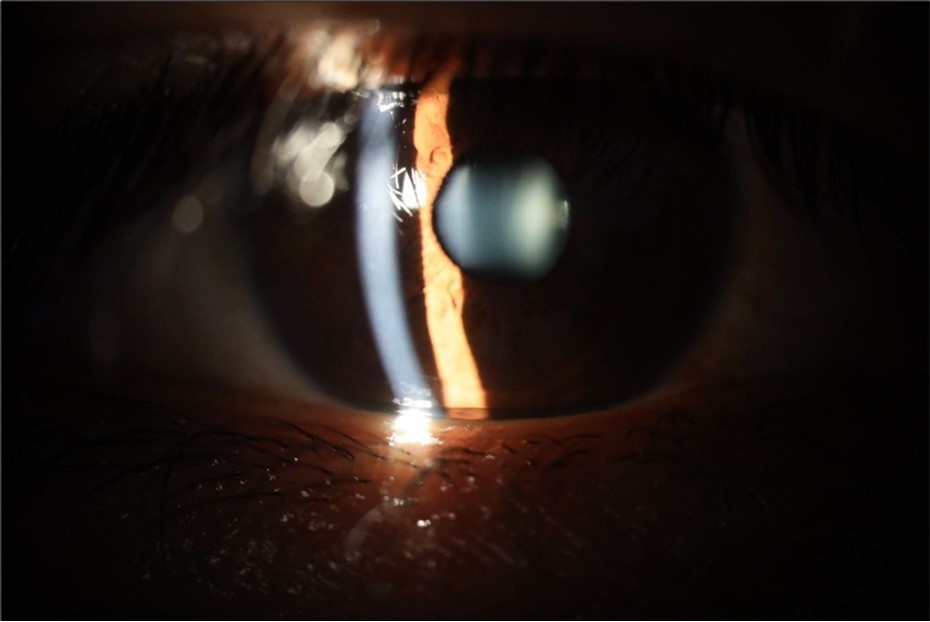

Figure 7.The photograph of the fundus of the right eye shows significant subretinal bleeding, which affects the entire macular area; and some blood is also seen in the vitreous body.

The photograph of the fundus of the right eye shows significant subretinal bleeding, which affects the entire macular area; and some blood is also seen in the vitreous body.

Figure 8.The photograph of the superior temporal region of the retina of the right eye shows the extent of subretinal bleeding as well as retinal edema.

The photograph of the superior temporal region of the retina of the right eye shows the extent of subretinal bleeding as well as retinal edema.

Figure 9.The extent of bleeding, mainly subretinal, is extensive and of significant volume, suggesting choroid rupture in this area.

The extent of bleeding, mainly subretinal, is extensive and of significant volume, suggesting choroid rupture in this area.

Figure 10.The location of the bleeding is mainly subretinal, although blood is seen in minimal quantity in the vitreous body.

The location of the bleeding is mainly subretinal, although blood is seen in minimal quantity in the vitreous body.